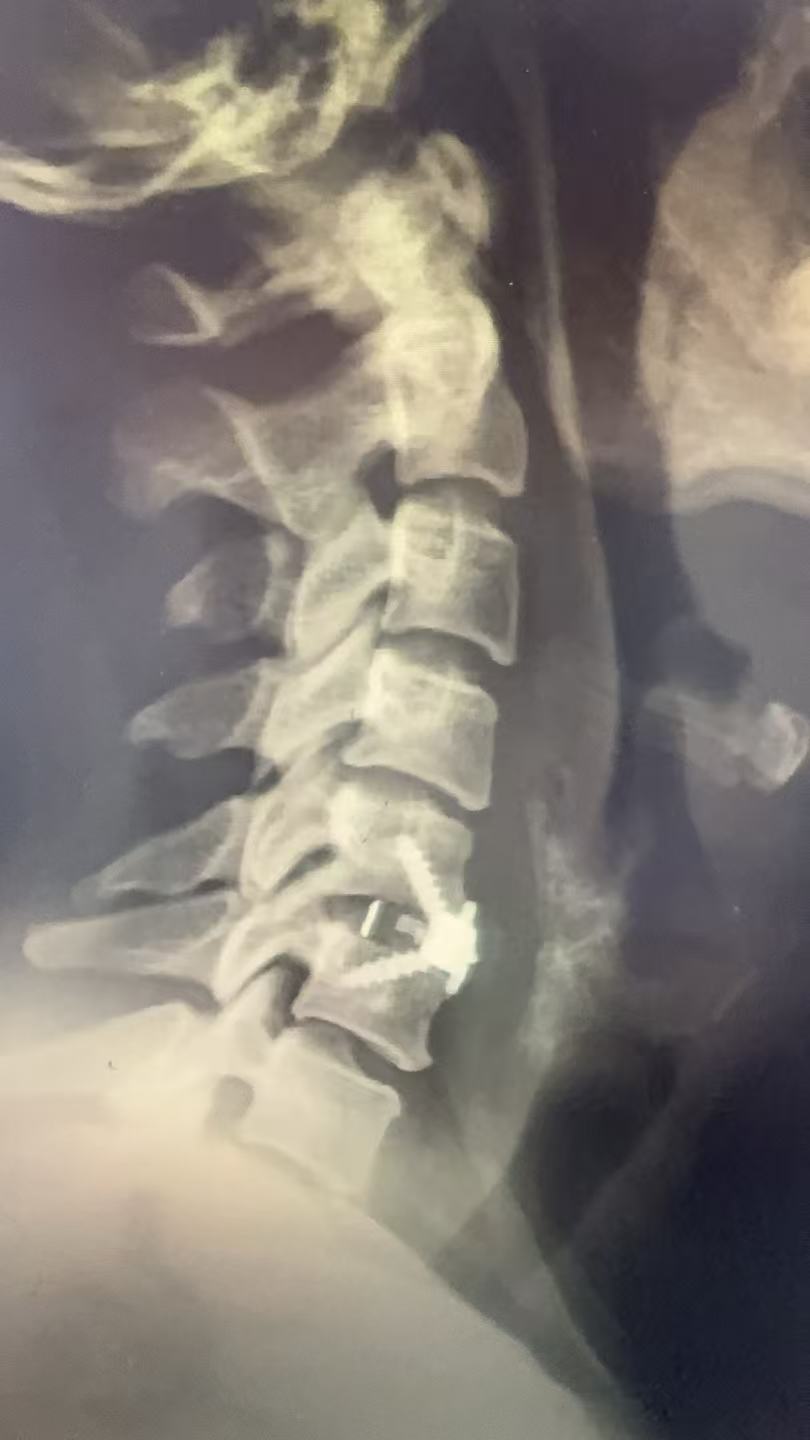

(术后图)

术后麻醉清醒后,陈女士即感颈部疼痛和手麻症状显著缓解。术后一天可在颈托保护下自主活动。